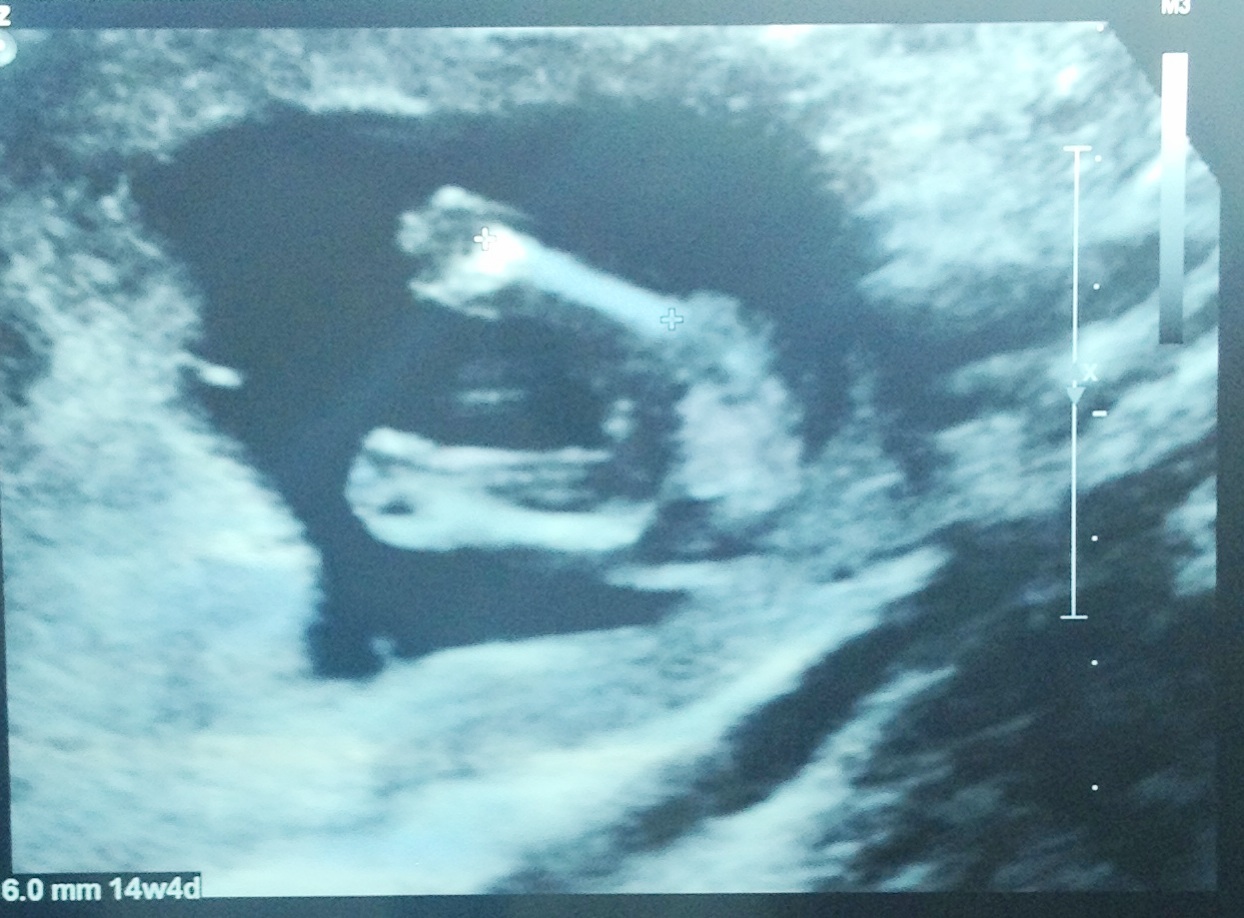

Hi ladies, had my scan today and tech clearly showed me 3 lines and then said not to get set on having a girl till my 20 week confirmation!!! What do you all think tho? Did anyone have a boy potty shot like this at 14 weeks 5 days?

Attachment 12848Attachment 12849